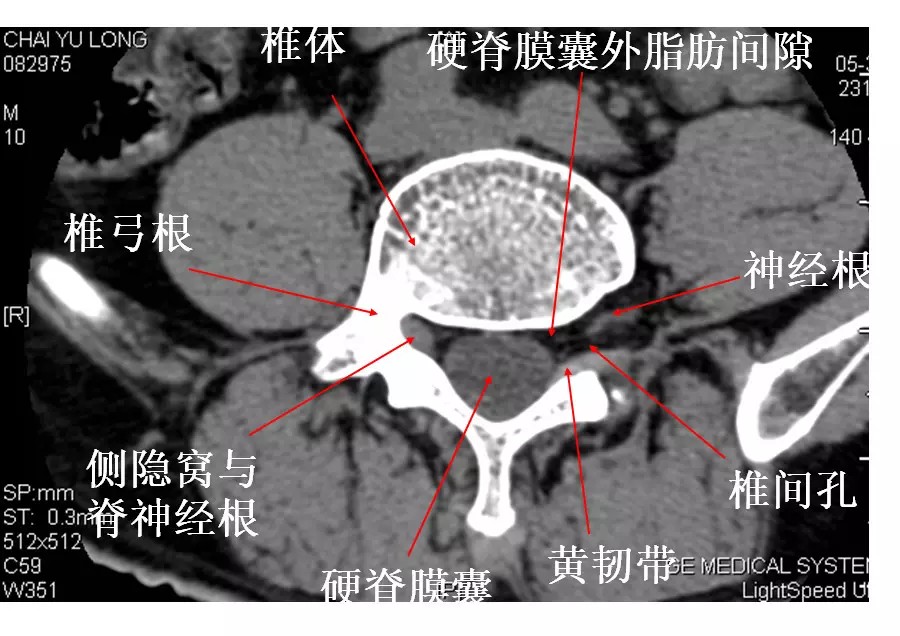

2.椎管及内容物

硬膜外脂肪:低密度影。

硬脊膜囊:呈圆形或椭圆形软组织密度影。CT平扫不能区别硬脊膜囊、脑脊液和脊髓。

椎内静脉丛:位于硬膜外间隙内,在CT平扫上不能单独显示,增强扫描呈点状高密度影。

3.椎间孔

位于椎管前外侧,其内的脊神经根呈软组织密度,周围有低密度的脂肪组织环绕。

黄韧带较厚(正常时≤3mm),位于椎板和关节突的内侧面,密度高于硬脊膜囊和硬膜外脂肪,显示较清晰。

椎间孔前为椎体,后为椎小关节,上下为椎弓根,内与侧隐窝相连,有脊神经根通过。

侧隐窝:向下外续于椎间孔,有脊神经经过:前壁为椎体后外缘;后壁为上关节突前面与黄韧带;外界为椎弓根。

正常前后径为3-5mm,<3mm侧隐窝狭窄>5mm,肯定不狭窄。